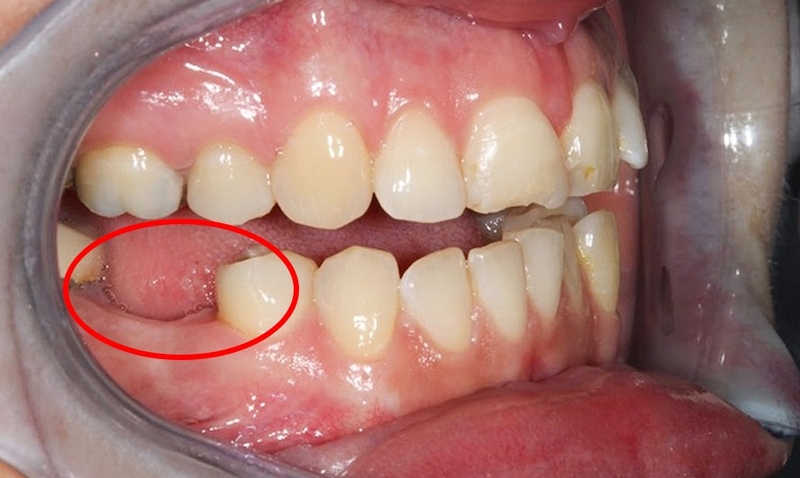

Răng số 6, răng hàm lớn nhất của con người, nằm ở vị trí thứ 6 từ răng cửa và thứ 3 từ cung hàm trở đi. Nó không trải qua quá trình thay răng sữa và chỉ mọc một lần trong đời. Chức năng chính của răng số 6 là nghiền nát thức ăn và hỗ trợ quá trình tiêu hóa diễn ra thuận lợi hơn.

Tuy nhiên, vị trí khuất trong cung hàm và kích thước lớn của răng 6 khiến cho việc vệ sinh răng trở nên khó khăn. Điều này dẫn đến nguy cơ sâu răng và các bệnh lý về răng miệng như viêm tủy răng, viêm chân răng. Do đó, chăm sóc răng miệng đúng cách là rất quan trọng để bảo vệ sức khỏe của răng số 6 và toàn bộ hệ thống răng miệng.

Mặc dù răng 6 đóng vai trò quan trọng trong cung hàm, nhưng vị trí khá khuất của nó khiến cho việc vệ sinh răng khó khăn, dẫn đến nguy cơ sâu răng cao và các vấn đề răng miệng khác.

Nếu răng sâu ở giai đoạn mới hoặc sâu răng vào tủy trong phạm vi vẫn có thể can thiệp được, bác sĩ sẽ ưu tiên phương án bảo tồn răng tối đa bằng cách lấy tủy răng hoặc trám răng. Tuy nhiên, trong những trường hợp sâu quá nghiêm trọng, việc nhổ răng số 6 là bắt buộc để tránh vi khuẩn lây lan rộng hơn sang các răng kế cận hoặc mô nướu gây viêm nhiễm.